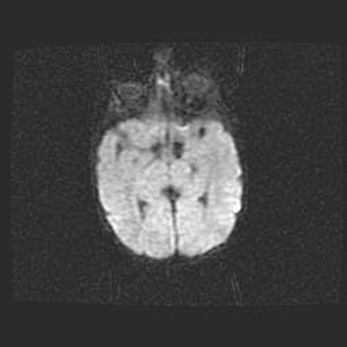

Церебральная ишемия II.

Возраст: 5 дней

Вес: 3400 г

Пол: женский

Окружность головы: 35 см

Срок гестации: 39 недель

Церебральная ишемия – это заболевание, характеризующееся недостаточностью (гипоксией) либо полным прекращением (аноксией) снабжения мозга кислородом по причине закупорки одного или нескольких сосудов. Это приводит к  что метаболическим расстройствам различной степени тяжести в тканях головного мозга, развитию коагуляционных некрозов и гибели нейронов.